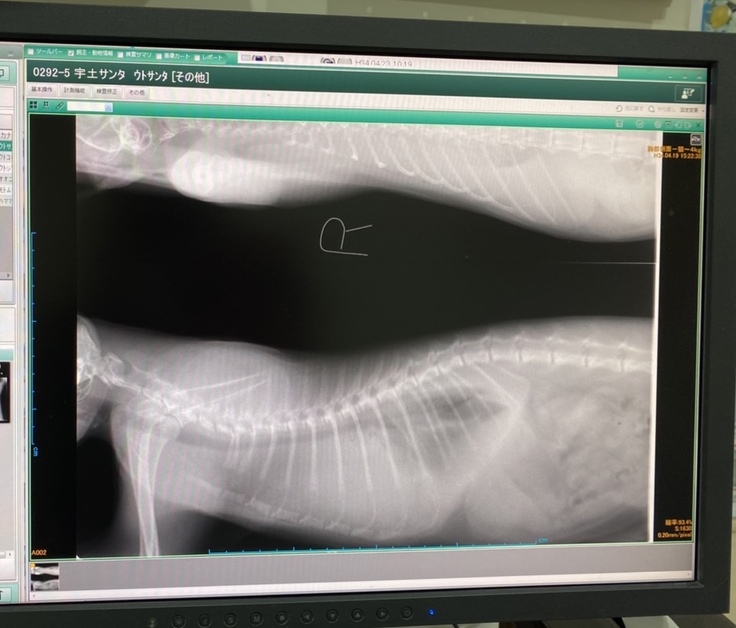

4月19日から、餌を食べず、呼吸困難の状態だった為、異変を感じ病院へ連れて行きました。

検査の結果「縦隔型リンパ腫」と診断を受けました。肺に4センチの腫瘍があります。胸水が貯留していたので、酸素吸入をしながら、胸水を抜きました。その処置をしたことで、息苦しさが改善されました。

心臓を挟んで両サイドに腫瘍が2つあるのですが、心臓の下の腫瘍がリンパ腫ではなく、胸腺腫の可能性があるとのことで、もし胸腺腫の場合は、再度治療方針が変わることもあるとのこと。

今回1回目の抗がん剤で、どれだけ腫瘍が小さくなっているかで確定診断になります。

<サンタのX線画像>